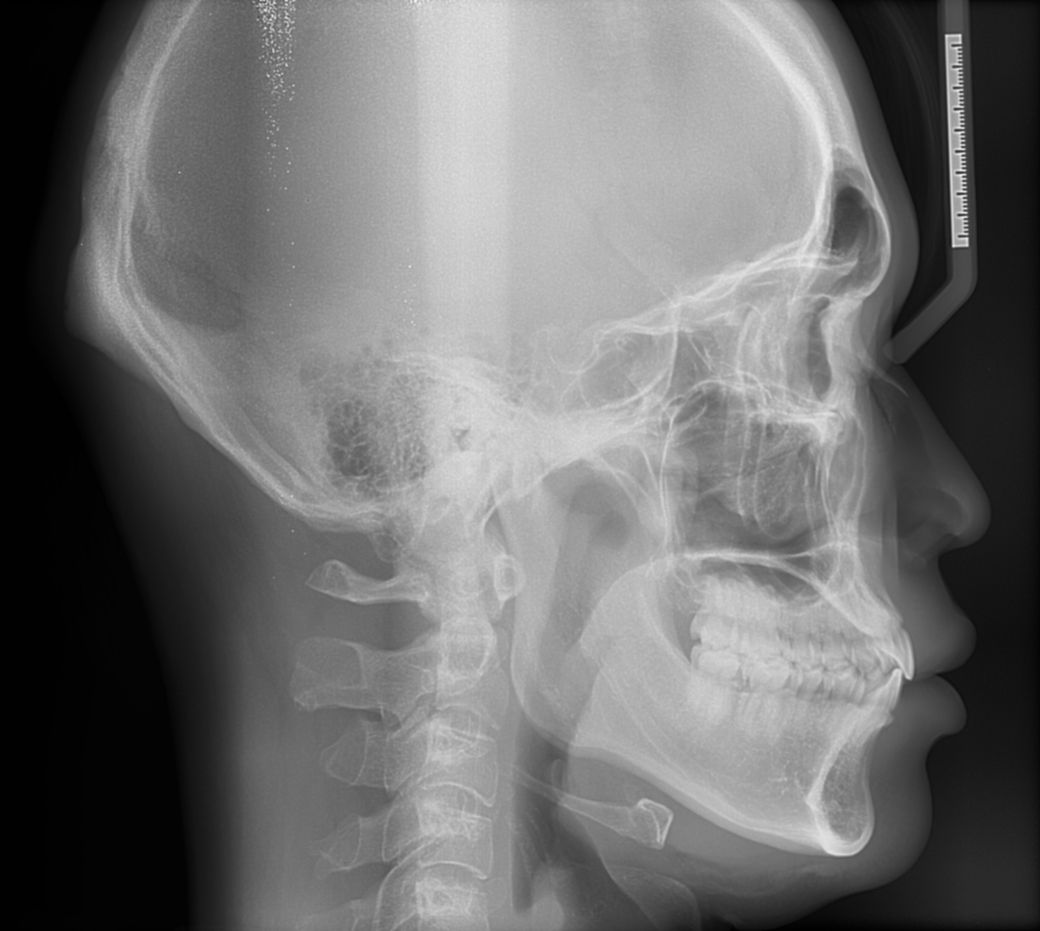

윗니가 아랫니를 덮는 양또는 윗니가 앞으로 나온양이조금 적다고는 하는데 골격적 문제라 어쩔 수 없다는데 맞나요?

부분 교정으로도 어려워 보이며 전체 교정도 현재 증상을 개선하기가 쉽지 않아 보입니다. 워낙 다른 부위에 치열 상태는 나쁘지 않기 때문에 교정을 하더라도 현재 증상에 대한 개선이 어려울 수도 있어 보입니다. 또한 치열 배열 뿐만 아니라 골격적 문제가 동반되고 있어 골격적인 부분은 교정으로 수정할 수가 없습니다.

지금 정도의 골격적 부조화는 일반인들은 알아차리지 못하며 양악 등을 수술을 권하는 정도도 아닙니다.